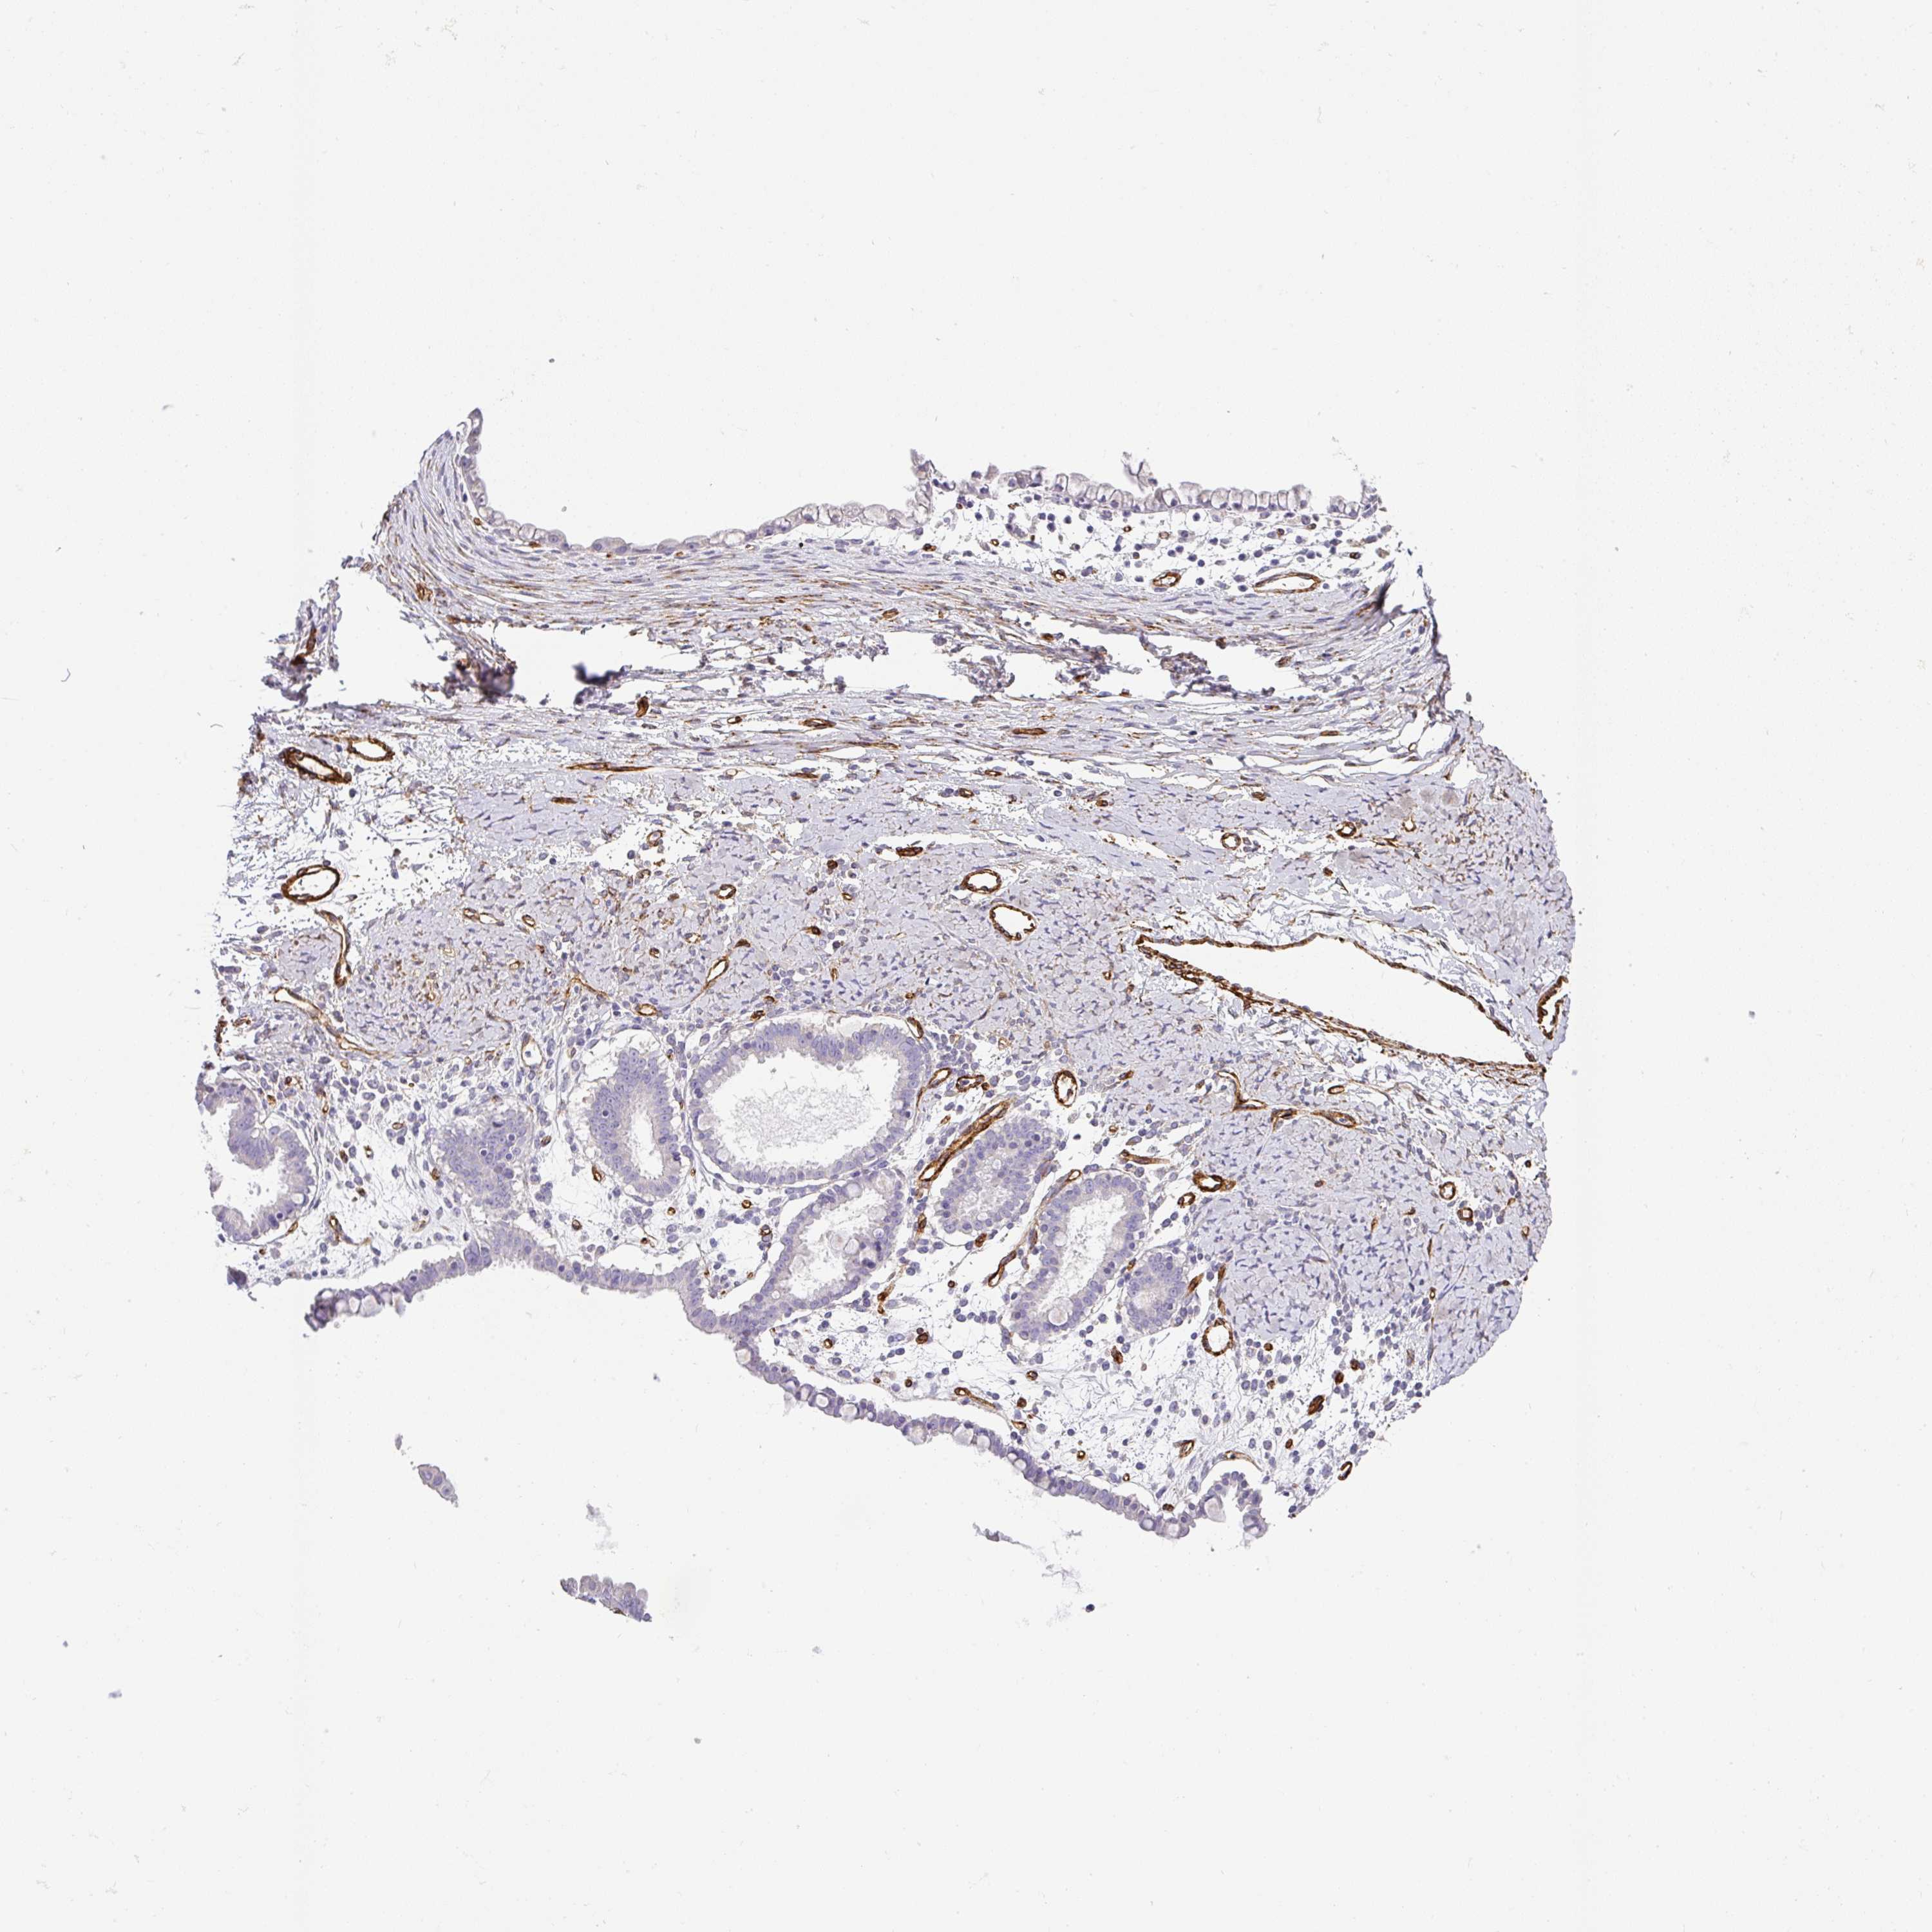

OVARIAN CANCER - Protein expressioni

A mouse-over function shows sample information and annotation data. Click on an image to view it in a full screen mode. Samples can be filtered based on level of antibody staining by selecting one or several of the following categories: high, medium, low and not detected. The assay and annotation is described here.

Note that samples used for immunohistochemistry by the Human Protein Atlas do not correspond to samples in the TCGA dataset.

Antibody stainingi

Antibody staining in the annotated cell types in the current human tissue is reported as not detected, low, medium, or high, based on conventional immunohistochemistry profiling in selected tissues. This score is based on the combination of the staining intensity and fraction of stained cells.

Each image is clickable and will lead to virtual microscopy that enables deeper exploration of all samples and also displays staining intensity scores, fraction scores and subcellular localization as well as patient and tissue information for each sample.

Antibody HPA052708

Staining

High

Medium

Low

Not detected

Intensity

Strong

Moderate

Weak

Negative

Quantity

>75%

75%-25%

<25%

None

Location

Nuclear

Cytoplasmic/membranous

Cytoplasmic/membranous,nuclear

Cystadenocarcinoma, serous, NOS

Cystadenocarcinoma, mucinous, NOS

Adenocarcinoma, NOS

Carcinoma, endometroid